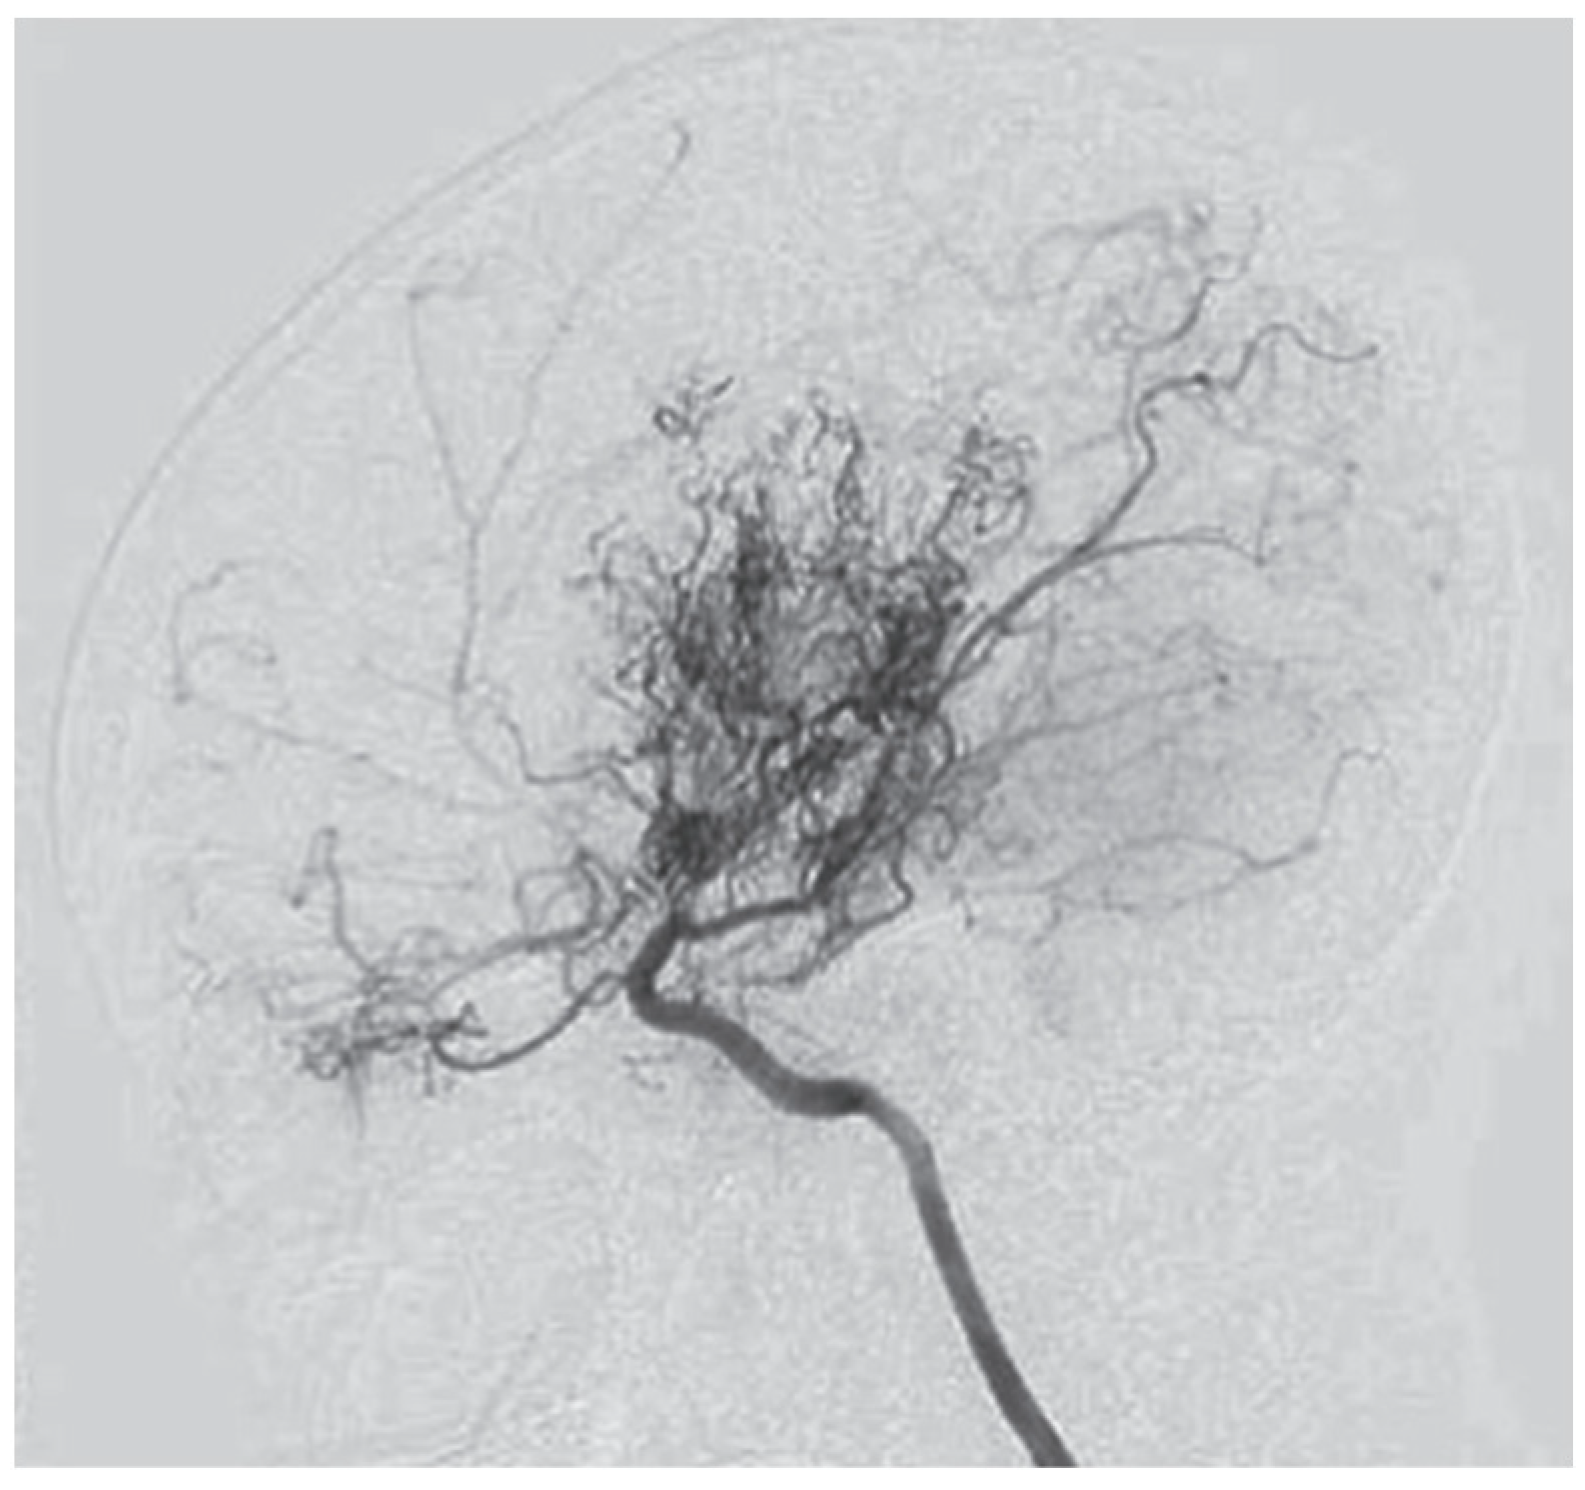

An MRI of the head (Figure 3) showed multiple long-standing ischemic lesions in all regions of the cerebral vasculature and significantly reduced blood flow in all arteries of the anterior circulation (Figure 4). Doppler ultrasonography of the extracranial vessels did not show any abnormalities. EEG revealed marked interhemispheric asymmetry—diffusely slowed, not well-organized brain activity in the right hemisphere, and in the left, not well-organized alpha rhythm with frequent single or multiple temporoparietal spikes. Abdominal ultrasound, consultation with a vascular surgeon, duplex ultrasonography of the lower limb vessels, consultation with a cardiologist, ECG, and echocardiography were all unremarkable for any pathology. Computed perimetry for the evaluation of visual field defects could not be accomplished due to excessive myopia, reduced visual acuity (20/800), and cognitive impairment. The serum level of valproate was 61.68 μg/mL.

Figure 3. T2-weighted MRI image showing diffuse ischemic lesion throughout the cerebral hemispheres.